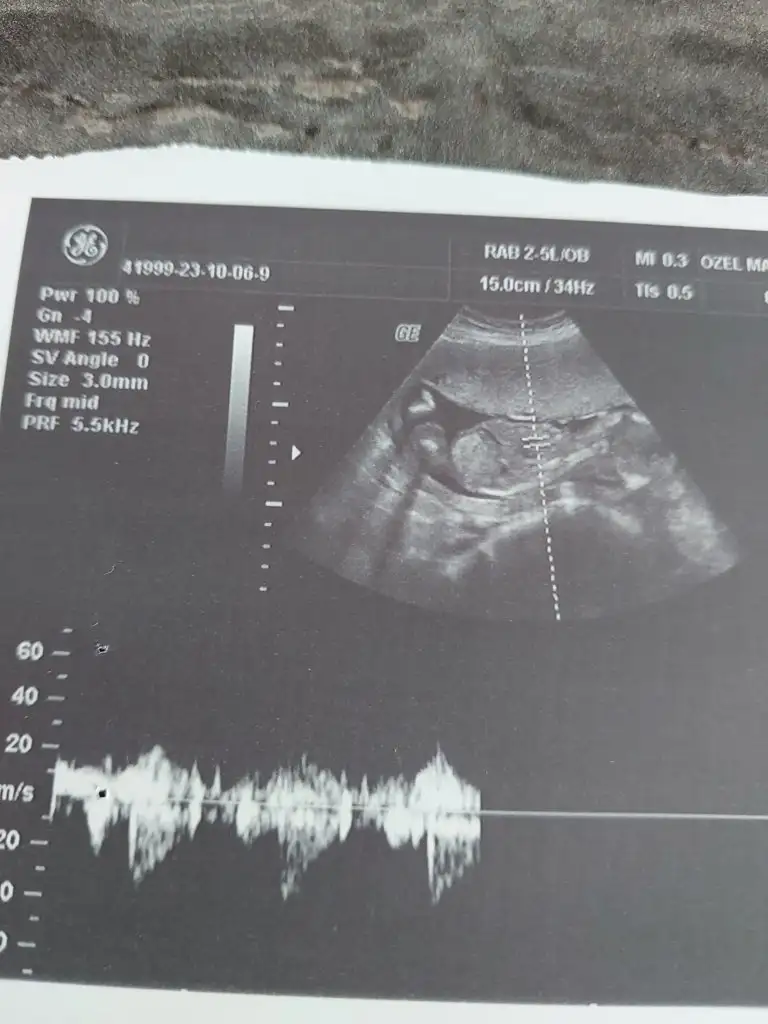

Sağlıkla gelsinBugün ki ultrason fotoğrafı

Kiz dedi doktorNeymiş cinsiyeti kuzunun